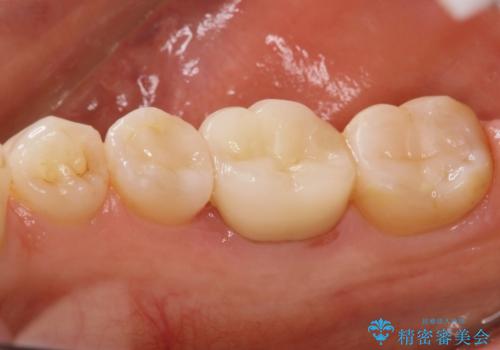

銀歯だったところは、歯質を削る量が多かったためクラウンにて治療し、前後の歯に関してはインレーにて治療を行なっております。

また、歯肉に関してもきれいに治って患者様も満足されていました。